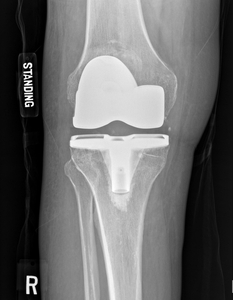

Physical exam demonstrates 0-110 degree range of motion of the right knee, tenderness and a small effusion of the right knee without warmth or erythema. No obvious skin pigment changes or brown-colored skin changes symmetrically on the cheeks typically seen with exogenous Ochronosis. He is 6 feet tall and 250 pounds. Preoperative x-rays and MRI are shown in Figures 1-10.

During a total knee arthroscopy intraoperative findings included gross blue/black discoloration of the cartilage surfaces of the distal femur, proximal tibia, and medial/lateral menisci [Figure 11]. There was eburnated bone in all three knee compartments. There was also blue/black hyperpigmentation minimally visualized in the synovial tissue. Postoperative pathology report demonstrated the same gross findings and hyperpigmentation of the cartilage. Postoperative work-up included culture/gram stain and urine organic acid testing. These tests all returned negative.

His postoperative course progressed as expected. He developed postoperative edema and had a negative doppler ultrasound. His physical therapist’s final report demonstrated 0/10 pain, 0-120 degree range of motion, and all goals met by > 90%.